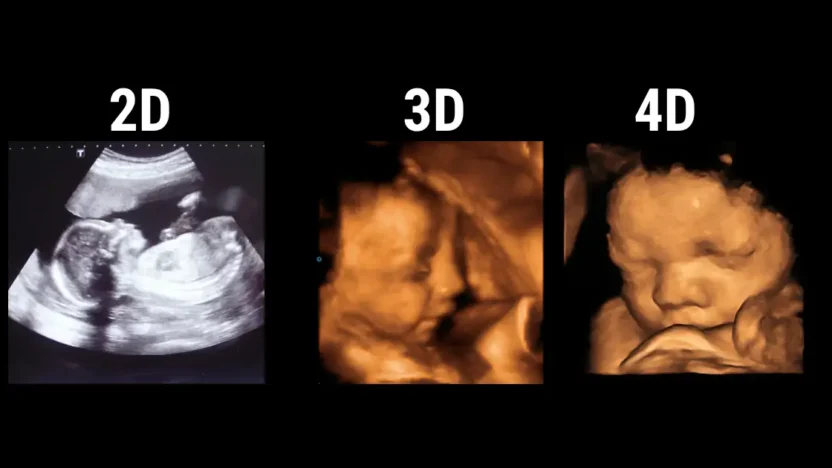

Jenis-jenis USG Fetomaternal

Jenis-jenis USG Fetomaternal | Sumber: eHealth Community

Pemeriksaan ini tidak hanya terbatas pada satu teknologi, melainkan menggunakan kombinasi berbagai jenis USG untuk mendapatkan gambaran kesehatan janin yang paling lengkap dan akurat.

2. USG 3D/4D

Ilustrasi USG 3D/4D | Sumber: Lux Radiology

Jika USG 2D memberikan "potongan" organ, maka USG 3D menyatukan potongan-potongan tersebut menjadi gambar statis tiga dimensi yang jelas.

Sementara itu, USG 4D menambahkan elemen waktu, menghasilkan video real-time yang memungkinkan Anda melihat janin bergerak, menguap, atau mengisap jari.

- Identifikasi anomali permukaan: USG ini sangat efektif untuk mendeteksi kelainan struktural pada permukaan tubuh janin, seperti bibir sumbing (sumbing palatum), kelainan bentuk hidung, atau deformitas pada anggota gerak.

- Korelasi klinis: Gambar-gambar ini sering kali membantu orang tua dan dokter memahami kondisi janin secara visual, yang sangat membantu dalam perencanaan intervensi setelah kelahiran.